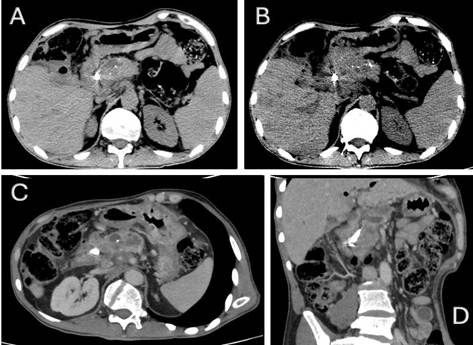

Subsequent CT scans demonstrated no significant changes in the pancreatic mass (Figure 2). However, magnetic resonance imaging (MRI) performed ten months after symptom onset revealed a persistent hypovascular mass with diffusion restriction in the pancreatic head and uncinate process, measuring approximately 4.9 cm in its largest diameter. This was associated with marked upstream dilation of the main pancreatic duct (up to 13 mm) and findings consistent with splenomesenteric venous junction thrombosis with collateral vessel formation, raising strong suspicion of an underlying pancreatic adenocarcinoma superimposed on focal pancreatitis.

Figure 2. Contrast-enhanced abdominal computed tomography. (A) Expansile lesion with interspersed calcifications in the pancreatic head (arrow) accompanied by body atrophy. (B) Biliary stent in situ within the common hepatic duct. (C) Lesion encasing the splenomesenteric venous confluence. (D) Coronal reformat demonstrating craniocaudal tumor extent